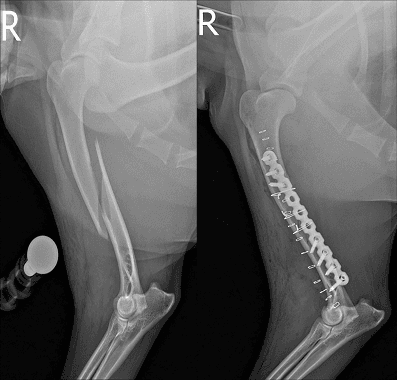

부러지거나 휘어진 뼈를 다루는 수술은 단순한 조립 과정이 아닙니다. 비비동물병원은 뼈가 스스로 붙을 수 있는 생물학적 환경(혈류)을 철저히 보존하고 국제 표준 원칙(AO)에 기반한 정교한 수술 계획으로 아이의 빠른 일상 복귀를 이끕니다.

단순 골절부터 복합 골절까지 뼈의 형태와 관절 침범 여부를 다각도로 읽어냅니다. 아이의 골격에 맞춘 완벽한 계획이 수술 시간을 줄이고 안전성을 높입니다.

세계적인 정형외과 표준인 AO 원칙(AO Principle)을 엄격히 준수합니다. 아이가 체중을 싣고 걸어도 뼈가 흔들리지 않도록 생역학적 안정성과 기능 회복을 동시에 잡습니다.

부러진 뼈를 맞추기 위해 근육을 광범위하게 절개하지 않습니다. 수술 중 C-arm(실시간 방사선 투시 장비)을 활용하여 뼈의 정렬과 스크류의 위치를 실시간으로 확인하며 절개창은 최소화하고 수술의 정확도는 극대화합니다.

수술 계획의 출발점입니다. 2방향(직교) X-ray를 통해 골절의 양상과 관절 침범 여부, 각기형의 다각도 변형을 오차 없이 정확히 파악합니다.

무작정 수술실에 들어가지 않습니다. 아이의 골격 구조를 면밀히 분석해 가장 튼튼하게 버틸 수 있는 플레이트 위치와 치유를 돕는 최적의 수술법을 미리 설계합니다.

수술 중 C-arm(실시간 투시 장비)을 통해 뼈의 정렬을 직접 확인합니다. 절개를 최소화하여 연부조직과 혈류를 보존하는 최소침습(MIPO) 방식으로 뼈를 안전하게 고정합니다.